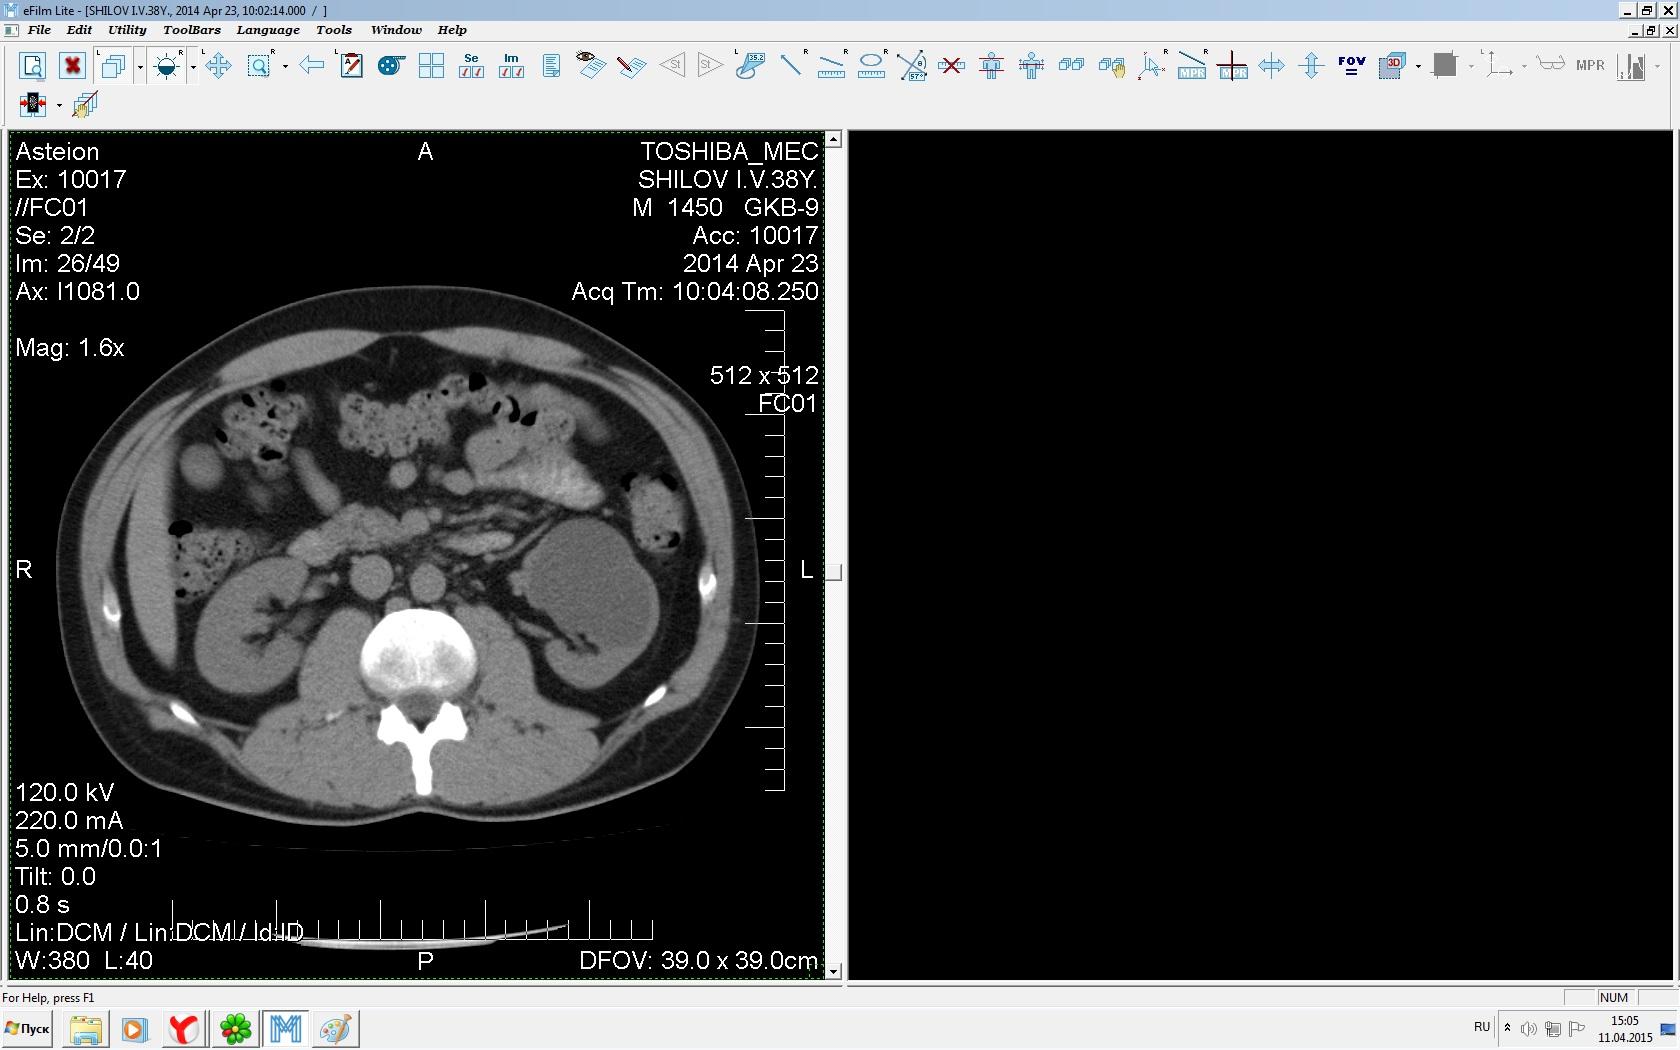

Здравствуйте. У меня киста левой почки. Из заключения: левая почка увеличена, деформирована за счёт наличия в среднем сегменте округлого жидкостного +6, +15 HU образования 66х53 мм, деформирует, поддавливает чаше-лоханочную систему. Сосудистые ножки структурные. В урологии мне сперва предложили лапароскопию, когда я лёг на операцию - изменили на полостную в связи со сложностью. Потом сказали что шансов вырезать кисту без почки практически нет. Даже если кисту удалить чудесным способом, то почка всё равно сложится и не будет работать. В итоге операцию отменили. Скажите, пожалуйста, есть ли современный метод удалить кисту и сохранить почку в моём случае? Томография почки в приложениях. Заранее благодарю.

Эту кисту можно просто пропунктировать, аспирировать и склерозировать - под местной анестезией. Ничего сверхестетственного не определяется по данным КТ. Можете написать мне на почту. aristova-tatyana@mail.ru